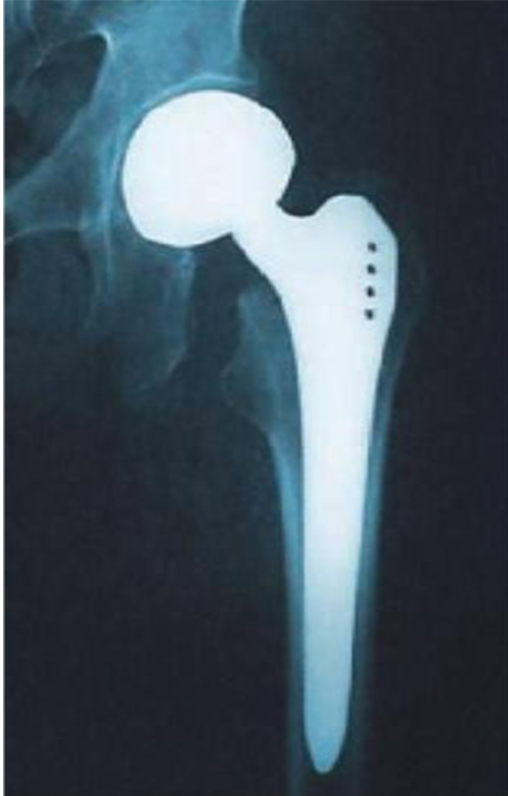

X-ray of a hip replacement

• hip prosthesis characterization and fatigue test